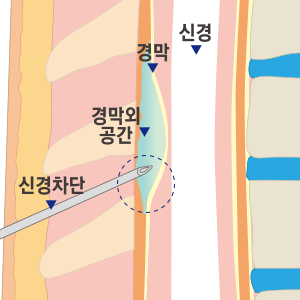

Treatment until the last painC-arm(특수영상치료장치)을 보며 치료하는 척추 비수술치료로 척추의 신경을 둘러싸고 있는 경막 바깥쪽에 약물을 투입하는 시술입니다. 허리 또는 목의 손상된 척추 부위에 가는 바늘을 통해 직접적으로 약물을 투입함으로써 신경 주위 염증과 부종을 가라 앉히며, 자율신경계의 정상적인 반응을 유도하는 치료입니다.

국소마취 하 디스크와 신경 사이에 정확히 바늘을 삽입하여 신경을 안정시키고 염증을 완화시킵니다.